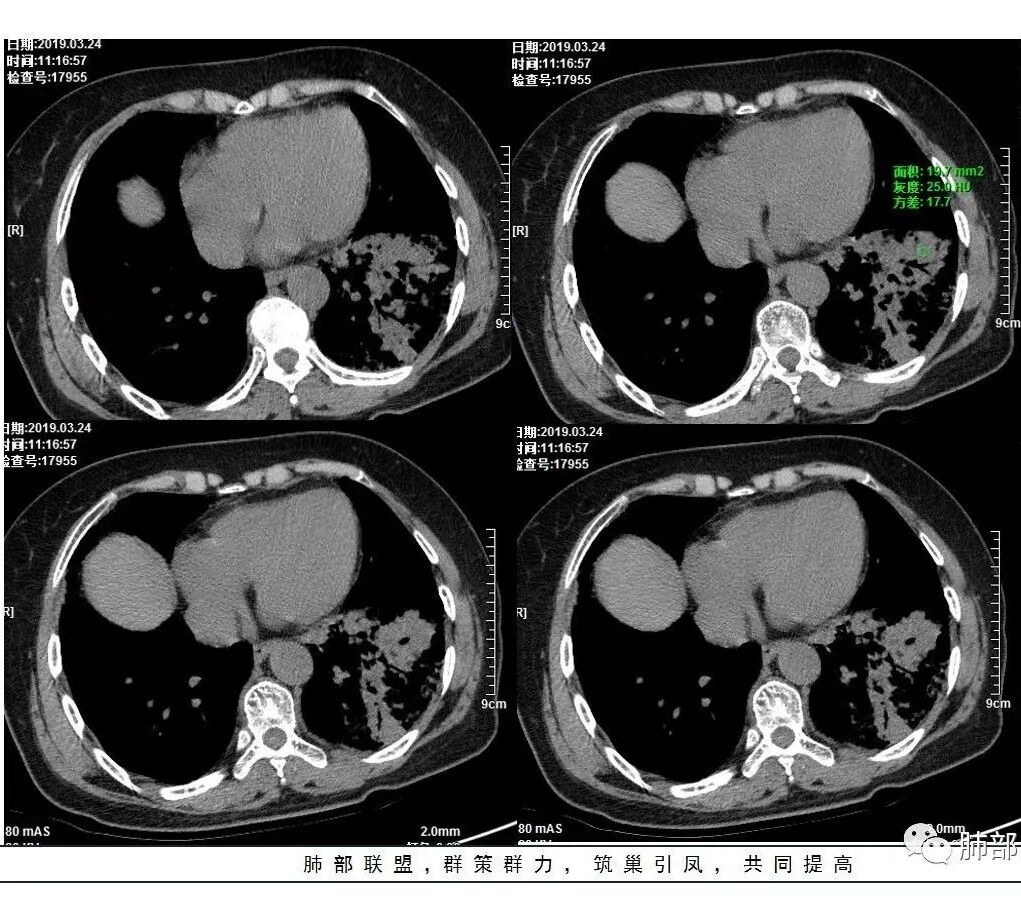

这是老问题:1、肺门区软组织密度影较弥漫;我们常规鉴别的就是结核?鳞癌?既往我们群里基本这两方向。2、弥漫的淋巴结钙化,加上马赛克灌注。马赛克灌注的原因是两个,一个是肺动脉的,一个就是小气道的问题。我们看增强的区域,没有看到栓塞,所以我倾向于小气道的问题,就是弥漫气道病变,慢性气道病变要考虑。我怀疑有没有淀粉样变性累及气道壁改变的可能。淀粉样变性是一个继发性病变,结核也可以,粉尘也可以。

这个病例支气管狭窄后扩张,肺门区有很多钙化的淋巴结,两肺弥漫的马赛克灌注,肺门淋巴结这么多,一个结核,一个尘肺,然后就是一个淀粉样变性,这几种最常见。鳞癌因为老年女性,除非吸烟,不太考虑,又不能绝对排除,所以就把鳞癌放到后。

今天这个病例有个明显的支气管狭窄,我倾向炎性,主要是和钙化淋巴结相关的,可能是继发的淀粉样变性。到底是什么感染,结核还是其他。我想看看复查后这个淋巴结,有没有突入到支气管腔内,如果有,他是继发于炎症的(比如中叶综合征,就是周围淋巴结压迫支气管,因为钙化淋巴结比较硬,支气管壁扛不住压力,突入支气管腔内,导致管腔狭窄,我们也称为结石征),如果没有,就和淋巴结关系不密切。之前有一例淀粉样变性的,淋巴结弥漫钙化,一种罕见的浆细胞型的CD。